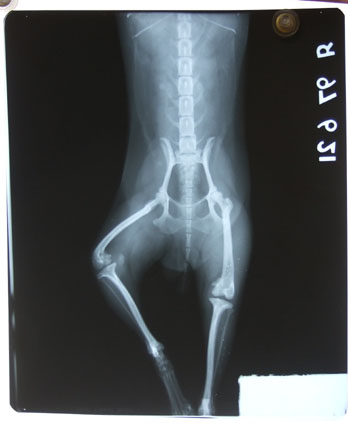

手術前,醫生先替茶茶拍X光片.

這是正面照.

變形的左後腿,兩隻腳骨已呈現90度扭轉變形,韌帶也完全萎縮.